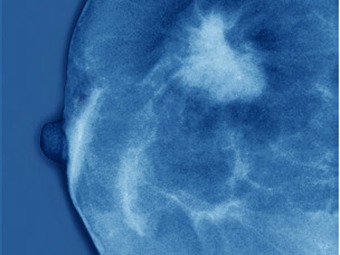

Revelan el misterio sobre el origen del cáncer de mama

En su estudio, publicado en la revista especializada Stem Cell Reports, explican cómo descubrieron que todas las mujeres -propensas o no a desarrollar cáncer de mama- tienen una clase particular de células normales precursoras con telómeros extremadamente cortos.

Los científicos se dieron cuenta de que estos cromosomas, al tener unos extremos tan pequeños, hacen que las células sean propensas a mutaciones que pueden desarrollar cáncer, si logran mantenerse con vida.

Cuando se pierde la función de los telómeros, cuya función es evitar que los extremos del cromosoma se junten o recombinen con otros, lo que ocurre es un verdadero caos en el siguiente ciclo celular.Si bien todas las mujeres tienen estos telómeros supercortos, no todas desarrollan cáncer de mama.